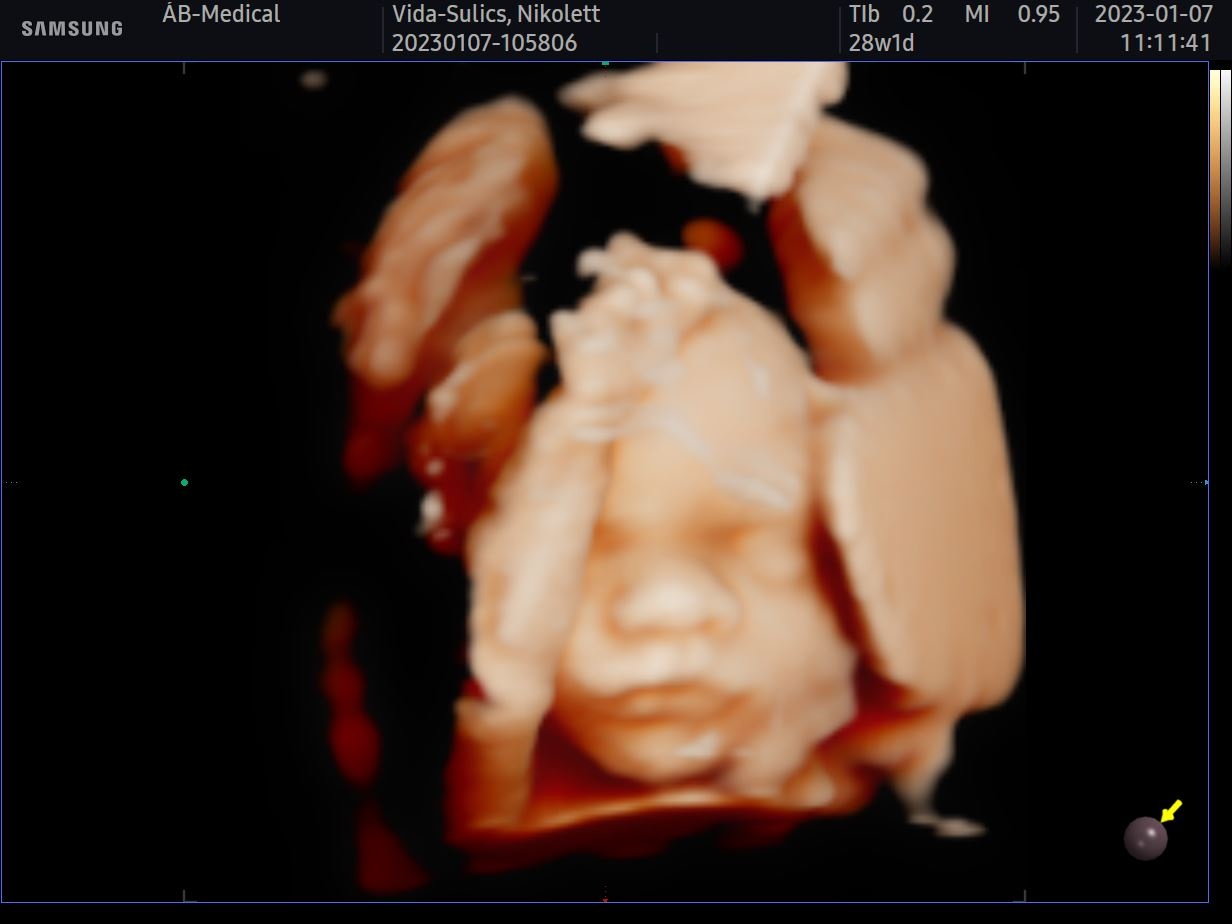

Szombaton babamozin jártunk egy nagyon kedves doktornőnél. Tavaly még teljesen felesleges pénzkidobásnak gondoltuk, így akkor nem jártunk ilyesmin. Idén elsősorban azért mentünk el, hogy legalább így láthassuk a babánkat, mert az előző kisfiunkat egyáltalán nem láttuk. Hatalmas élmény volt, legszívesebben minden nap elmennék és órákig nézegetném, hogy mit csinál odabent.

Ha még te is gondolkozol rajta, hát ne tedd, foglalj időpontot mihamarabb! Azóta is teljes extázisban vagyok és nem győzök betelni a fotók nézegetésével! Egyszerűen hihetetlen, hogy egy igazi kis emberi lény növekszik a pocakomban. Ahogy ígértem, hoztam nektek néhány fotót is.

Hamarosan nevet is illene választanunk már ehhez az édes kis pofihoz, de most valamiért nagyon nehezen megy. Nem találjuk az igazit,